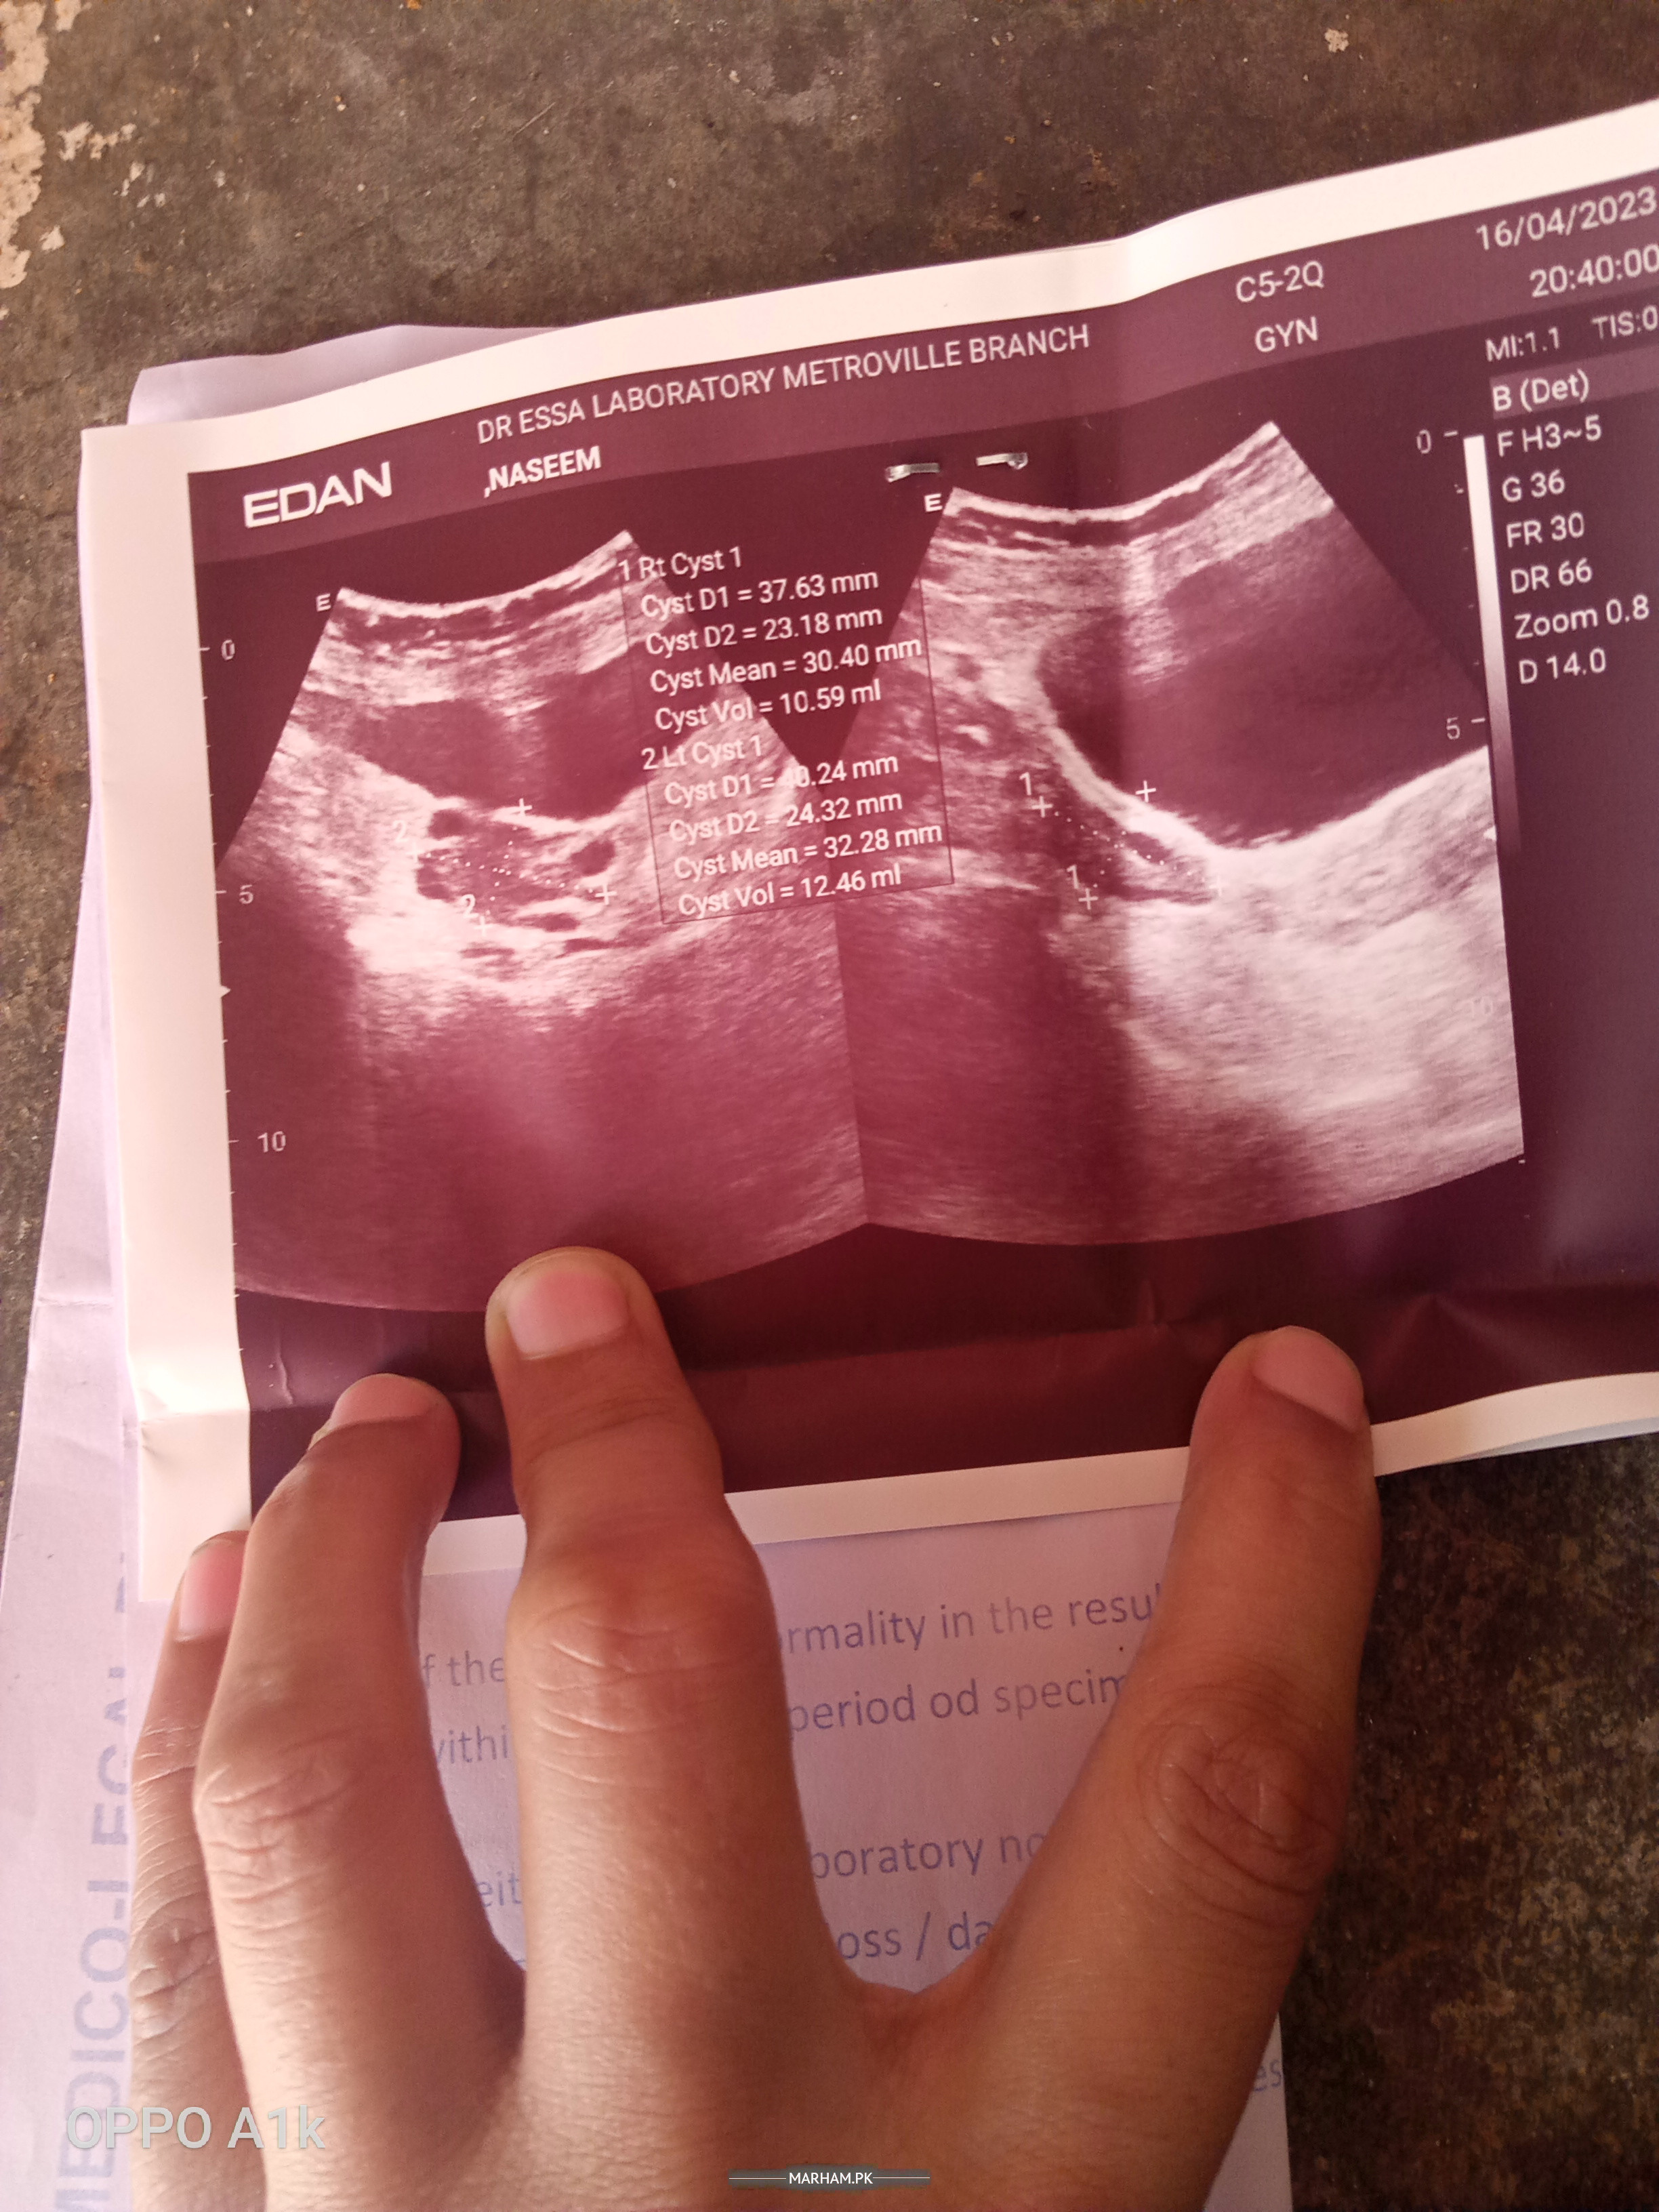

assalamualaikum Dr mjhy 2month sy continuesly bleeding horhi h ultra sound bhi krwaia h wo kehty hn Pani ki thelian hn usk Liye medicine bhi ly rhi but Bleeding nhi ruk rhi plz ko solution btain

share ur ultrasound reports

g send kr di h report

walecum assalam.bleeding amount?share ultrasound report .take cap transamine 500 mgx8 hrly tab ponston forte 1x8hrly

send kr di h report

ultrasound report